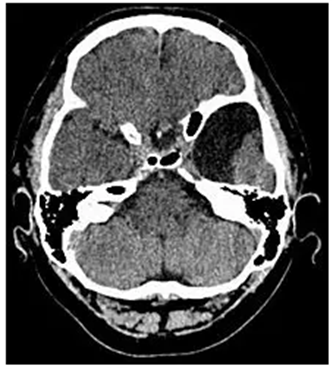

蛛网膜囊肿是一种常见的颅内良性病变,与肿瘤有本质的区别,男女无显著差异。蛛网膜囊肿可发生在蛛网膜下腔的任何部位,但以侧裂池(也称颞叶)蛛网膜囊肿最为常见。其发病机制是脑脊液在蛛网膜下腔流动受阻而形成的囊性病变。

蛛网膜囊肿可分为原发性蛛网膜囊肿和继发性蛛网膜囊肿。原发性蛛网膜囊肿由于与先天及发育因素相关,故多在青少年阶段之前被发现。蛛网膜囊肿大多没有明确症状,常为偶然发现,可在任何年龄阶段。典型症状有头痛头晕、头颅两侧不对称、不自主晃头、癫痫等。